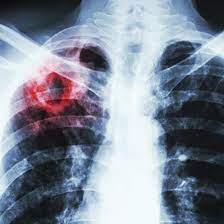

Öýkenleriň tuberkulýomasy

Öýkenleriň ojaklaýyn inçekeseli

Infiltratiw inçekesel

Incekeseliň etiologiýasy we patogenezi

Inçekesel zäherlenmesi

Inçekesel waksinasy

Disseminirlenen inçekesel

Inçekeseli anyklamak